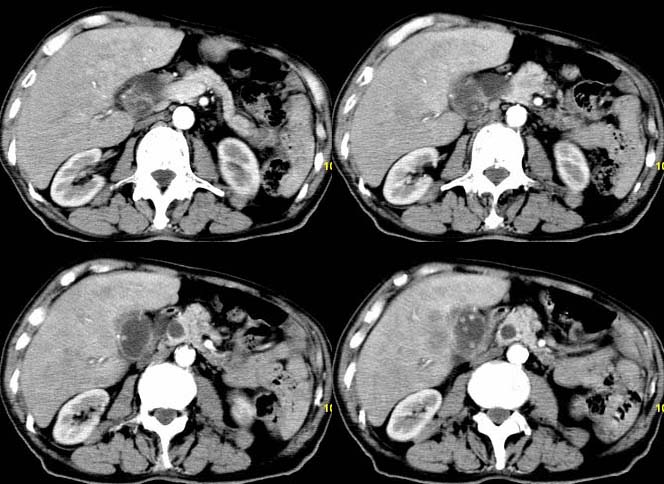

以下是引用余辉在2007-12-6 22:23:00的发言:[br]胆囊内多枚结石影,胆管全程扩张,右肝内病灶强化符合脓肿表现现(左肝病灶图像未传完),考虑急性梗阻性化脓性胆囊胆管炎合并肝多发脓肿(建议补传左肝病灶图像)